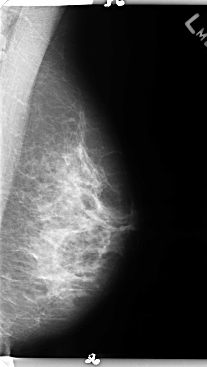

B_3156_1.LEFT_CC

LEFT_CC LINES 4752 PIXELS_PER_LINE 2352 BITS_PER_PIXEL 12 RESOLUTION 50 NON_OVERLAY